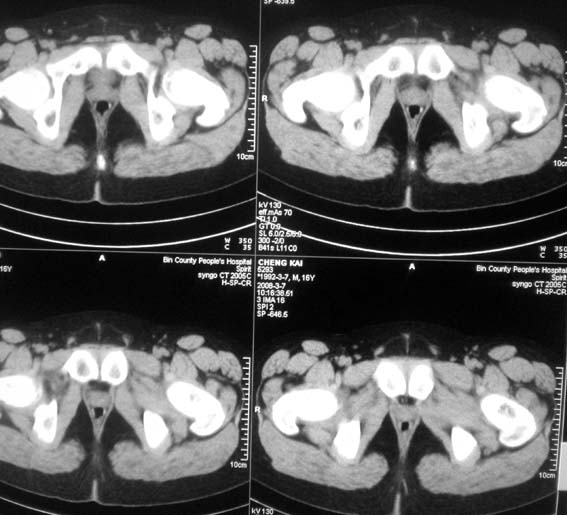

标题: CT12101:髋关节疼痛,请会诊。

男,16岁,髋部疼痛,发育延迟。

考虑:双侧髋臼发育不良性骨病。

双侧髋臼发育不良性骨病

双侧髋臼发育不良性骨病.股骨头早期坏死?

双侧髋臼发育不良性骨病(髋臼窝变浅,髋臼内上缘关节面毛糙)。

考虑:双侧髋臼发育不良性骨病